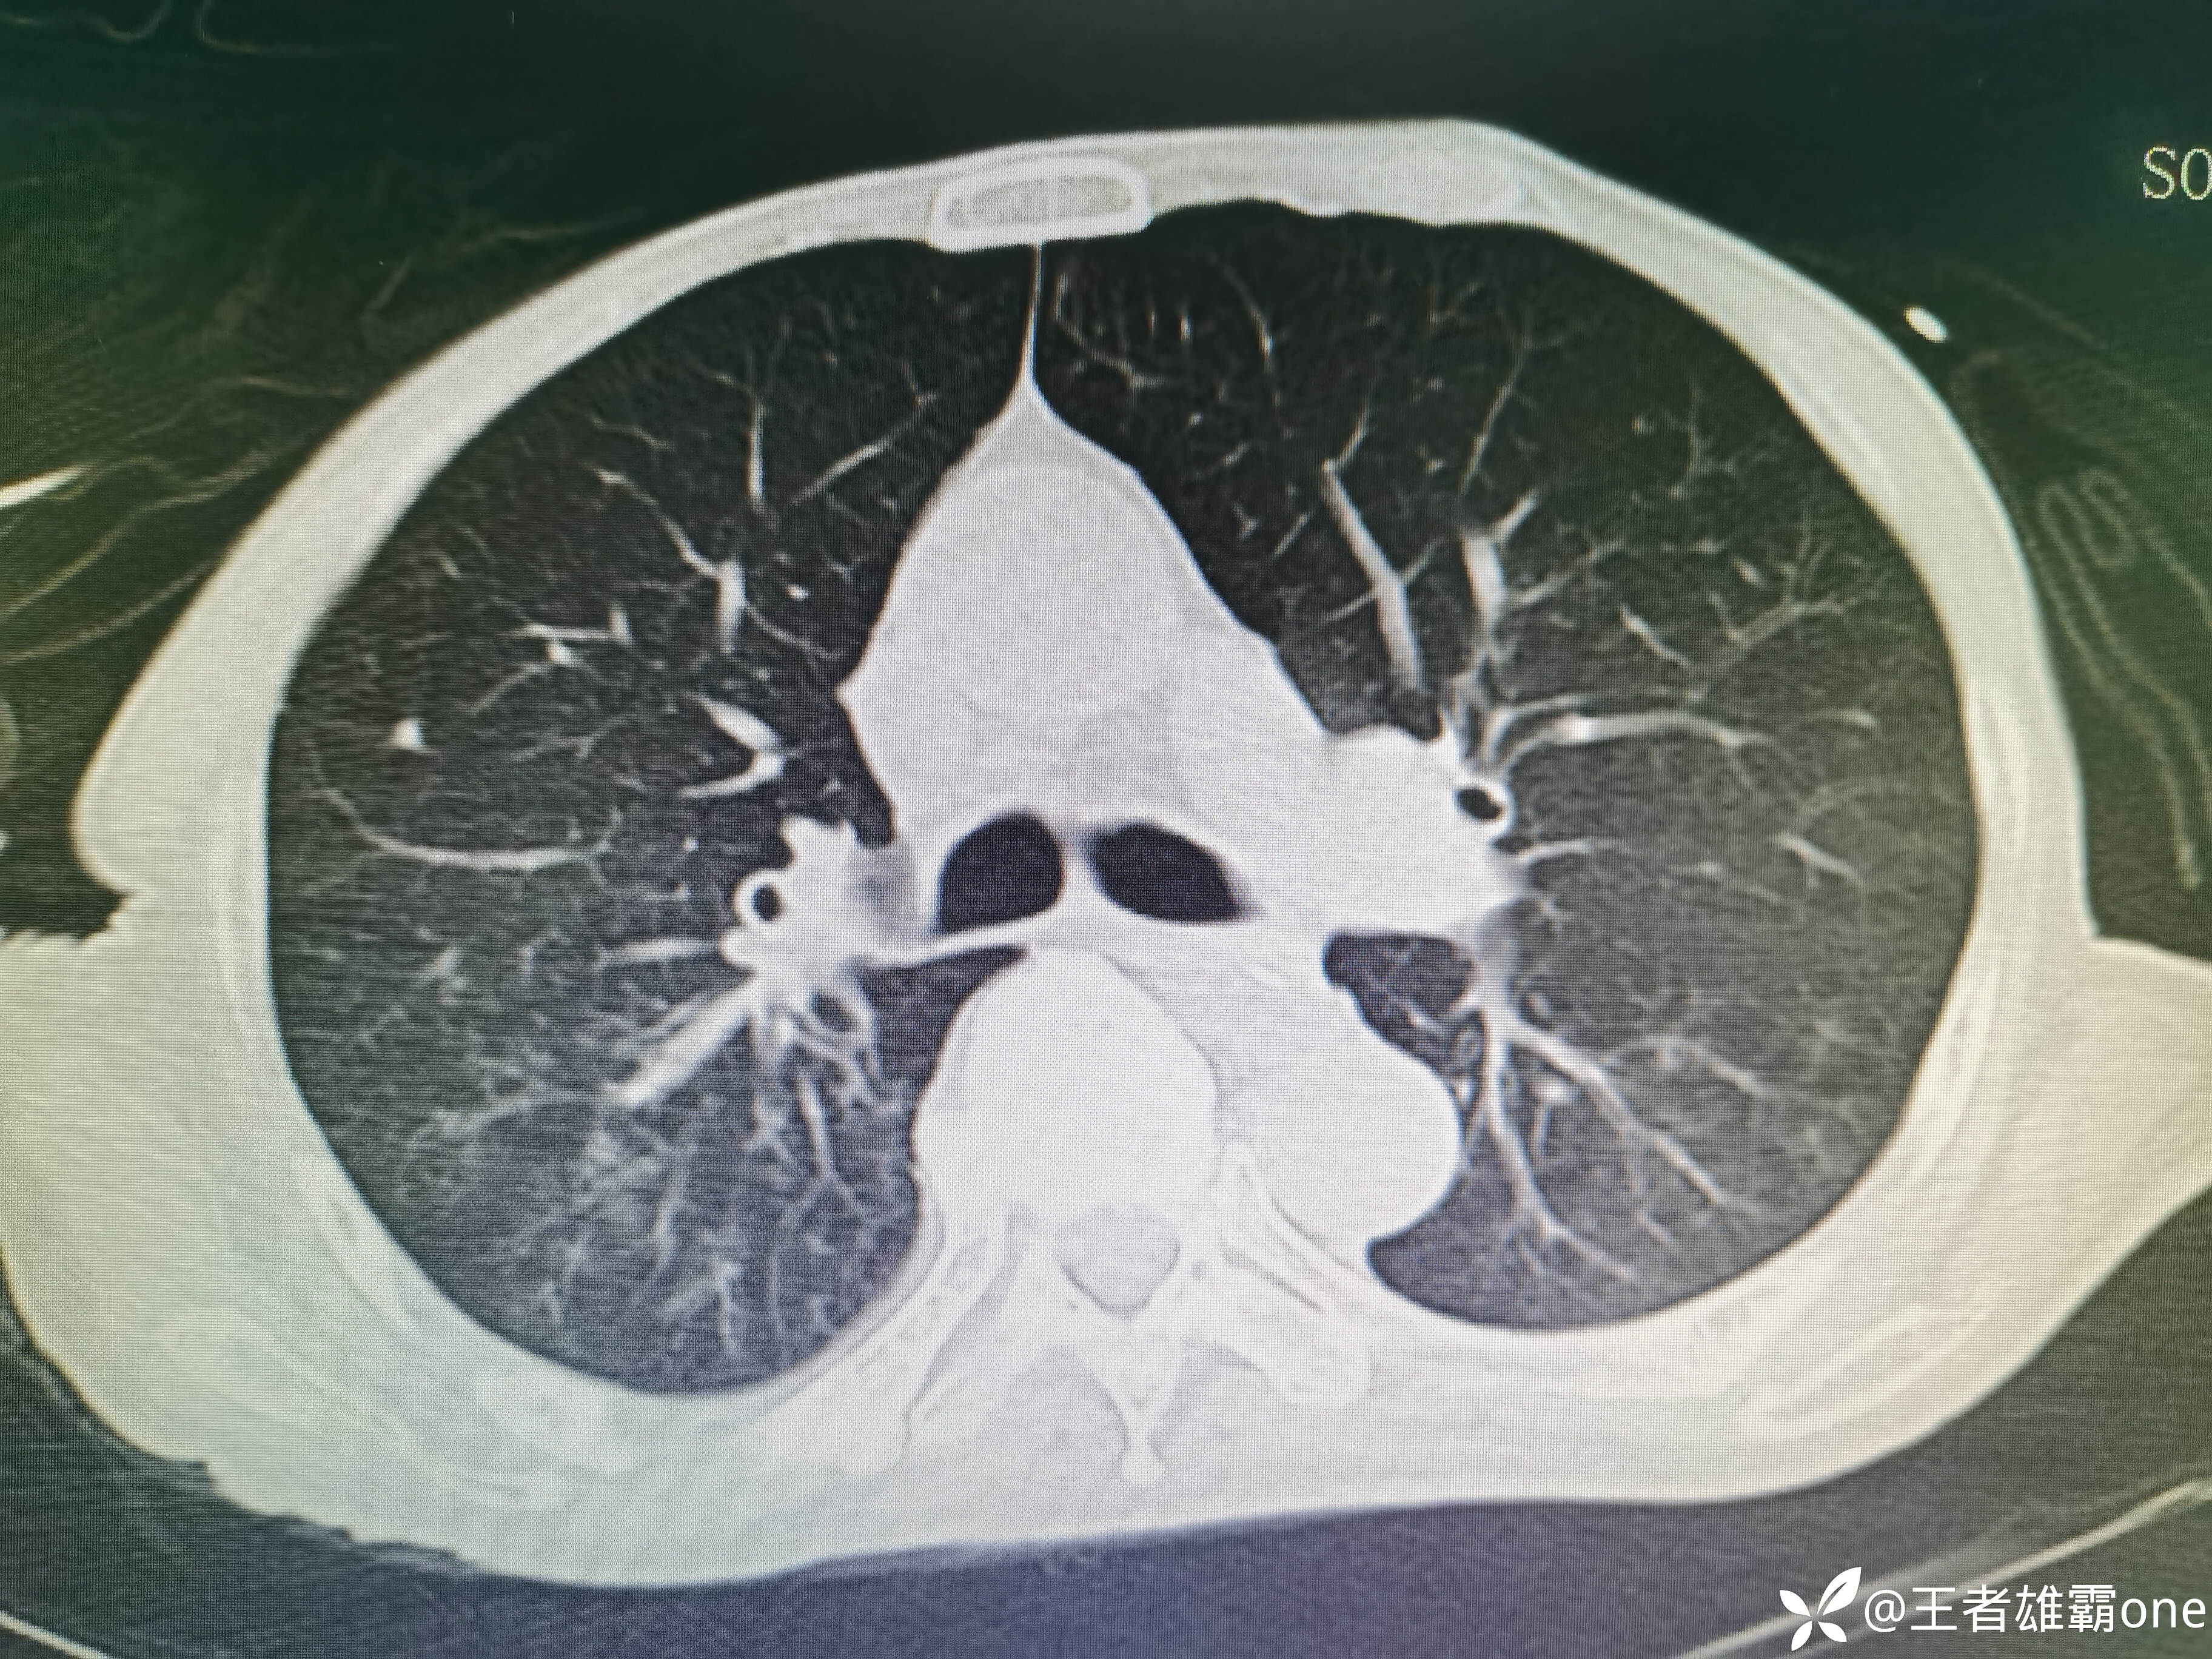

入院时胸部CT:

具体图片: